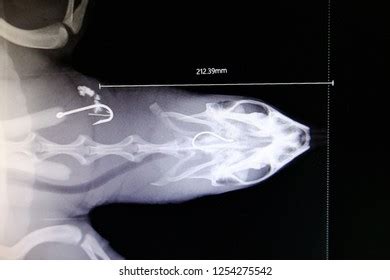

The craniocaudal view is less commonly used but can be helpful in certain situations, particularly when evaluating the turtle’s head and neck. The turtle is positioned with its head facing the X-ray tube, and the beam is directed from the cranial (head) end to the caudal (tail) end. This view can be challenging to obtain, as turtles tend to retract their heads into their shells. Gentle traction on the head and neck may be necessary to achieve adequate visualization. Use positioning aids to stabilize the turtle’s head and neck, and collimate the beam to include the area of interest. This view is useful for assessing skull fractures, cervical spine abnormalities, and foreign bodies in the esophagus.